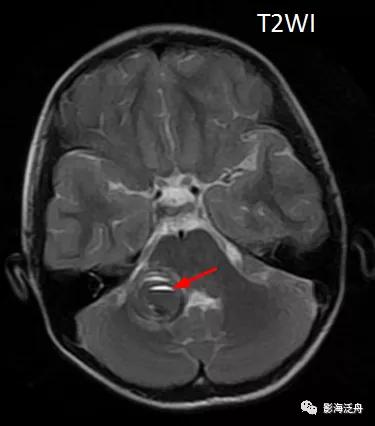

话不多说,上病例:患者女,12岁,头晕、头痛伴呕吐一天,无发热,无咳嗽,入院后行MR平扫检查,如下图↓↓

上图可见右侧桥臂一类圆形异常信号,T1WI呈中央稍低信号,边缘环形高信号,T2WI以低信号为主,局部可见液液分层(红箭),高、低b值DWI显示病变区域信号丢失。通过上述信号改变,不难看出是一个急性期血肿(血肿分期详见 MR上脑出血信号的演变机制)。